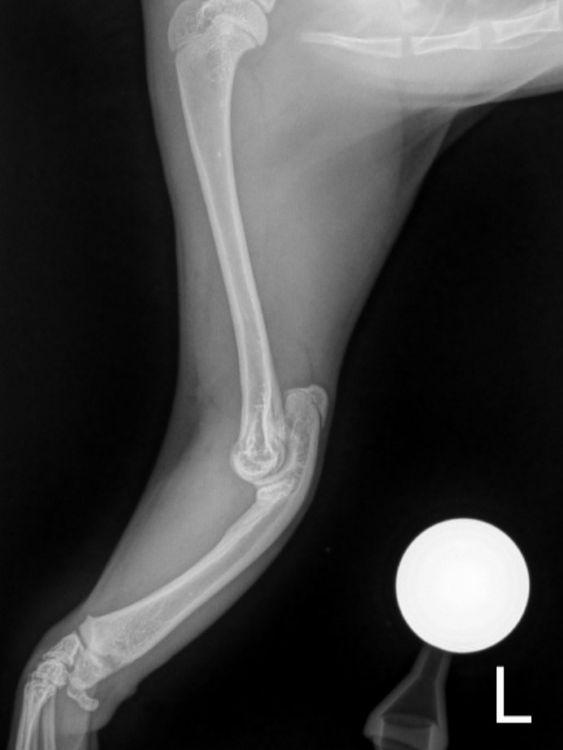

Vor drei Tagen bekamen wir die ersehnten Untersuchungsergebnisse für Pino. Seine Vorderbeine wurden in mehreren Schichten geröntgt und das Ergebnis muss man erstmal verdauen.

Es war sehr stark zu erwarten, dass es sich um eine angeborene Anomalie handelt. Und dies ist auch so. Pinos „Speichenknochen“ (Radius) fehlen auf der linken Seite ganz, auf der rechten Seite ist er unterentwickelt. Das führt dazu das seine Füßchen mit den Ellenbogen nicht stabil verwachsen sind und die Gelenke nicht festsitzen. Dadurch wachsen auch die Knochen nicht entsprechend und haben krankhafte Veränderungen. Der kleine Mann wird seine Vorderbeine nie richtig belasten können, so wie es im Moment aussieht. Ein normales Katzenleben in Freiheit ist für ihn in diesem Zustand unmöglich. Gott sei Dank zeigen sich aber keine andere Anomalien in seiner Anatomie.

Sofort nach der Diagnose haben wir begonnen uns in Spezialkliniken in Deutschland umzuhören, um einen fachmännischen Rat zu bekommen. Wenn Pinos Wachstum abgeschlossen ist, gibt es chirurgische Möglichkeiten, Fuß- und Ellenbogen Gelenke zu stabilisieren. Dies ist aufwändig und nur von Spezialisten durchführbar.